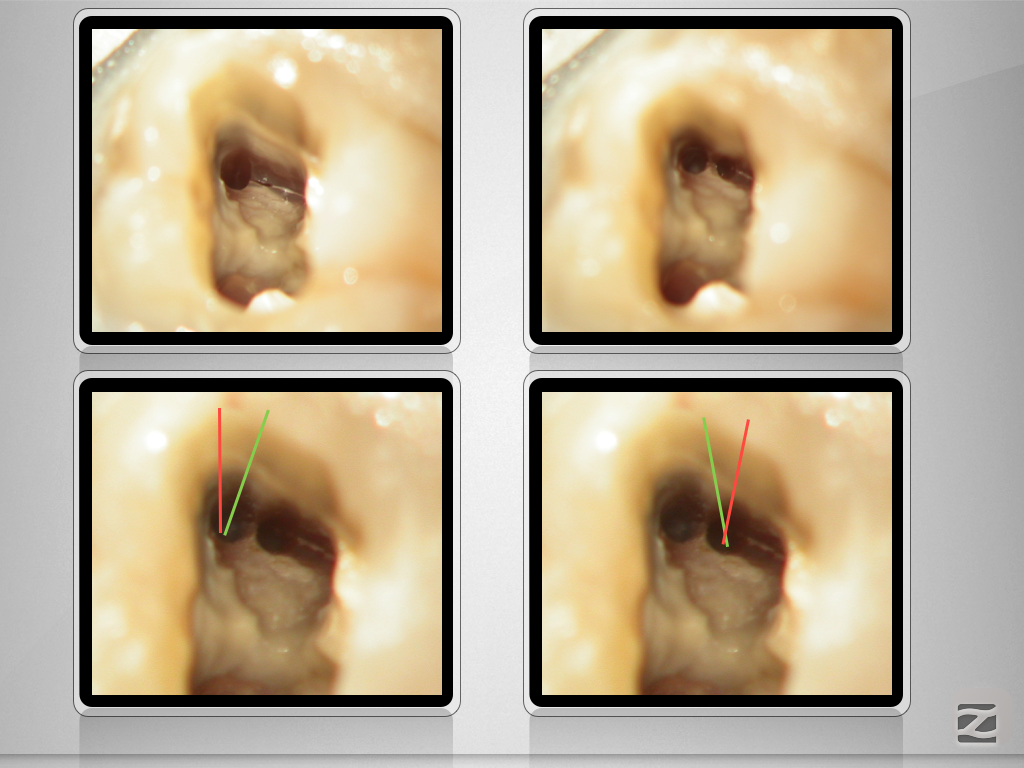

X-Bein- mit Überlegung zum Erfolg